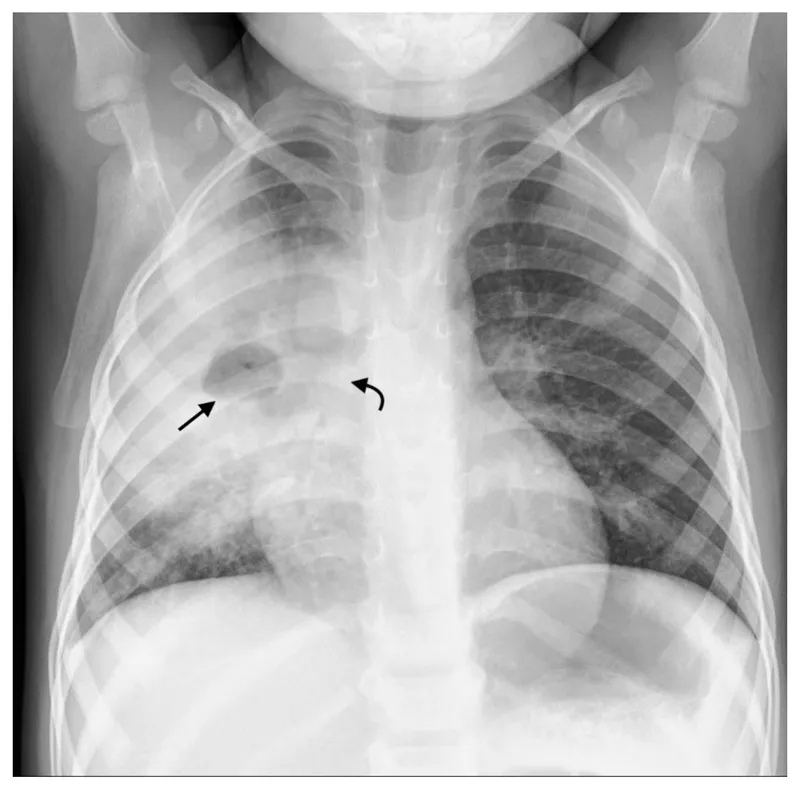

- Bronchopneumonia (Patchy):

- Pattern: Patchy, segmental, or lobular consolidation

- X-ray/CT: Multiple foci of opacity, often bilateral, peribronchial thickening.

- Bronchopneumonia: Manifests as patchy, segmental consolidations, often multilobar.